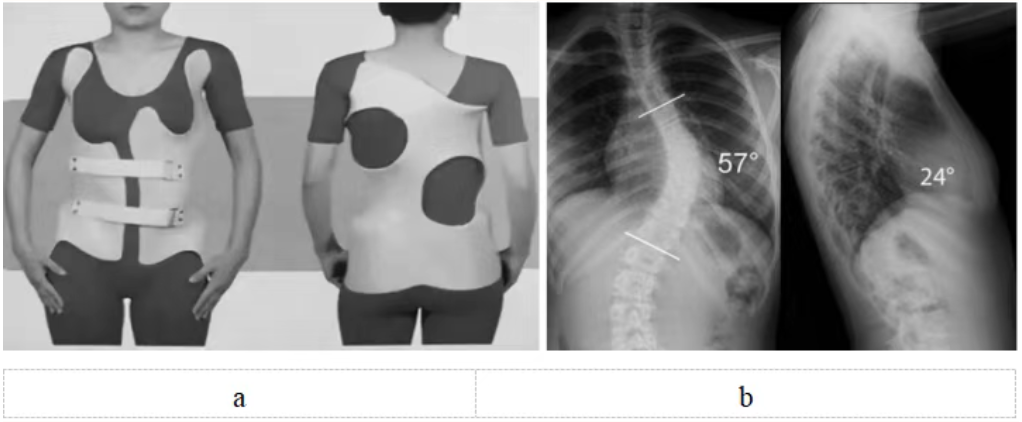

脊柱側彎支具治療需專業定制(圖5),日用型每天佩戴20小時以上,夜用型需整晚佩戴。初期可能有不適,需1~2周適應期,要注意皮膚護理。必須堅持佩戴至骨骼發育成熟,通常需要2~3年。矯正效果取決于佩戴時長和持續性,家長要做好監督。

圖5 a:特發性脊柱側彎(中度)配戴支具正面觀和背面觀;b:特發性脊柱側彎(重度)X線正側位,需要手術治療。注:a和b非同一患者

重度側彎(Cobb角>40度)(圖5):